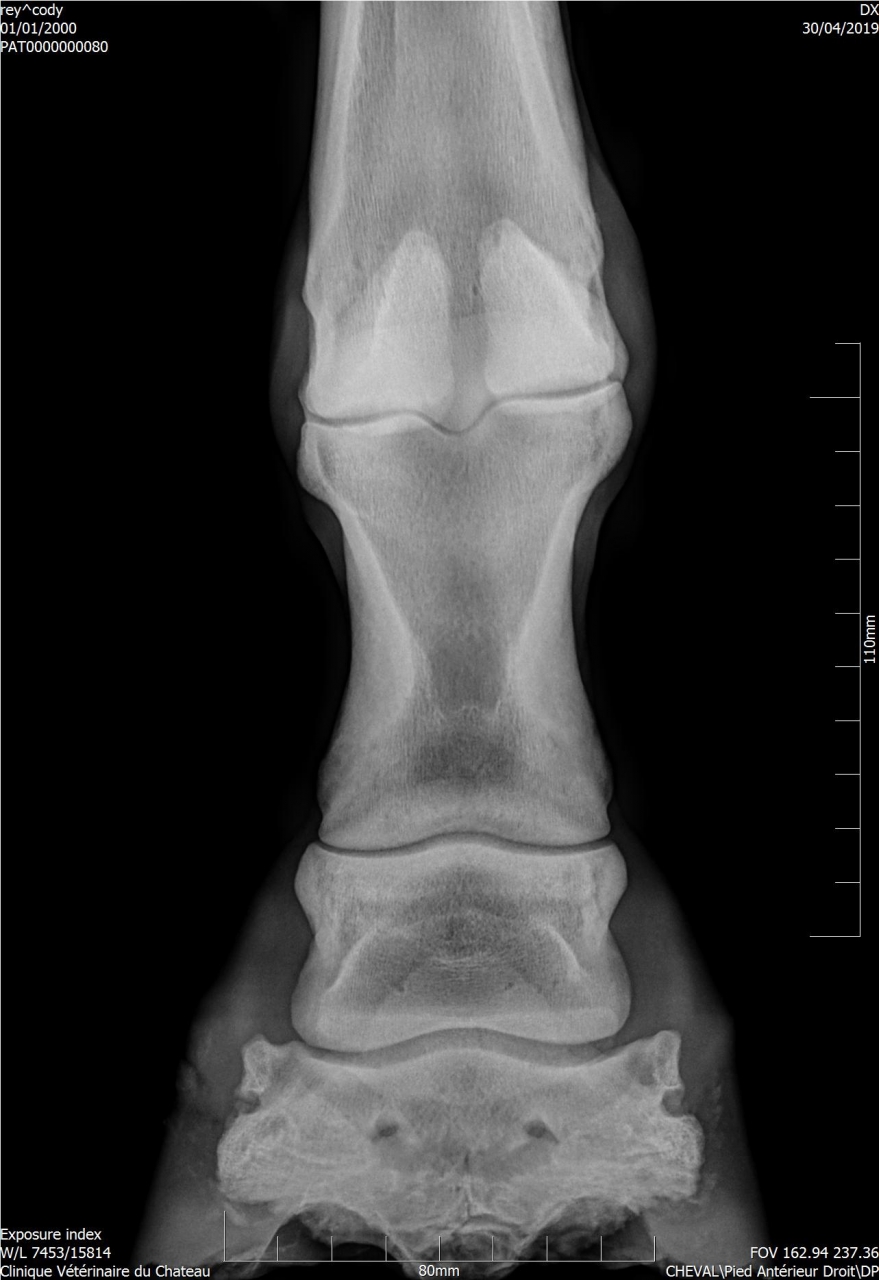

| Dire merci | Pour donner un ordre d'idée : radio de Cody.![]() |

| Dire merci | Disons que ça dépend ce qu'il voulait voir, s'il voulait les articulations c'est bon, s'il voulait une photo du pied c'est coupé c'est clair ! Mais je pense qu'il cherchait une photo des articulation, sur une photo de pied l'articulation du boulet est souvent coupée (cf radio de cody) Elle est bizarre d'ailleurs ta radio goss, on voit pas du tout la boîte cornée |

| Dire merci | La radio a été prise pour voir le naviculaire. J'en ai d'autres ![]() ![]() ![]() |